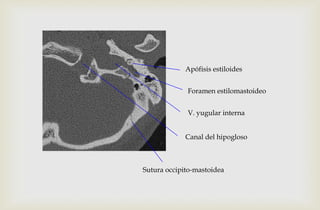

Apófisis estiloides

Foramen estilomastoideo

V. yugular interna

Canal del hipogloso

Sutura occipito-mastoidea